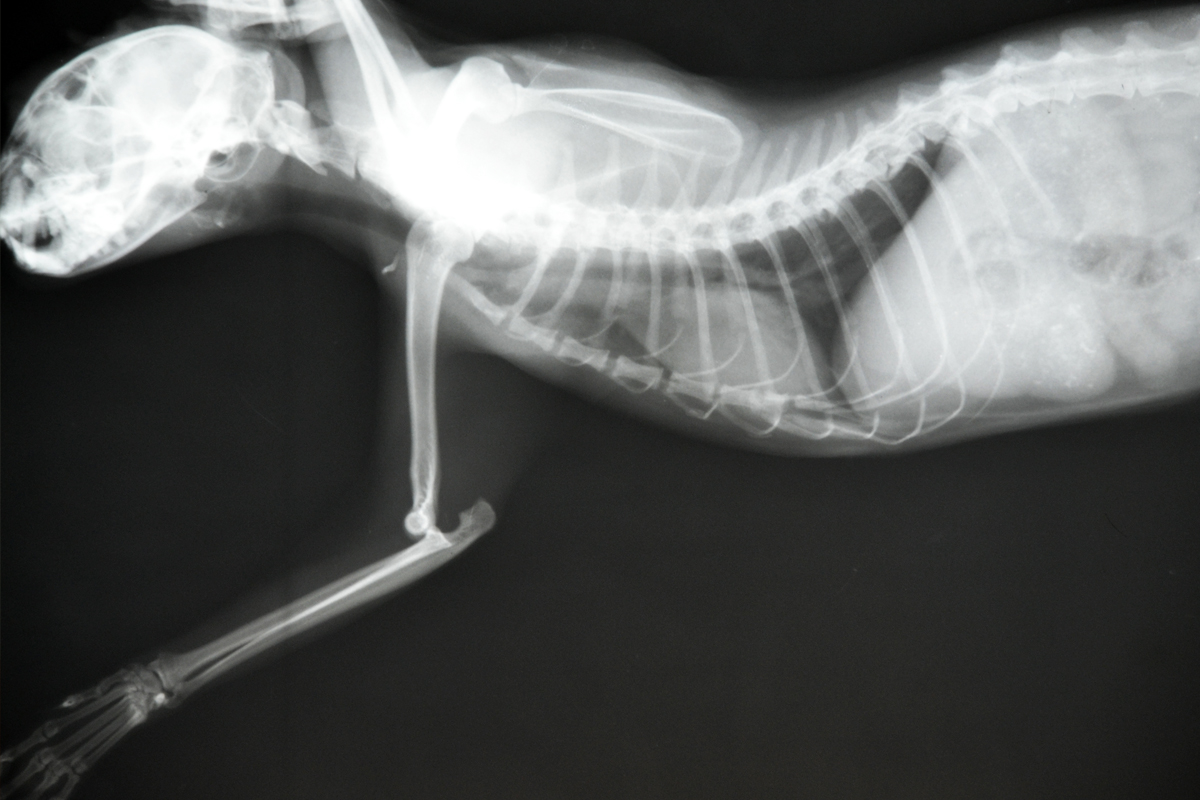

Рентгеновские снимки головы кошки в боковой проекции